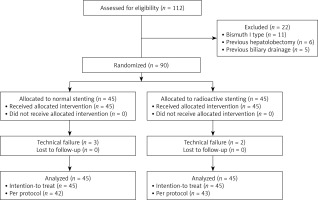

Between April 2021 and March 2022, 90 patients with HC were randomly assigned to either a normal or a radioactive stent insertion group (n = 45/group). Patient baseline data are summarized in Table I, while a flowchart of the study process is provided in Figure 1. To be eligible for inclusion, patients had to: (1) have a definitive diagnosis of HC, (2) have inoperable HC, and (3) exhibit symptoms consistent with obstructive jaundice. Patients were excluded if they (1) had Bismuth I type IC, (2) had undergone perioperative external radiotherapy, (3) had any prior history of biliary stent insertion or drainage, (4) had any history of prior hepatolobectomy, (5) exhibited an Eastern Cooperative Oncology Group (ECOG) performance status (PS) ≥ 4, or (f) were unable to provide informed consent.

Patients were randomized to normal and radioactive stent groups at a 1 : 1 ratio via block randomization with a block size of four. Random numbers were generated with a computer and placed in sealed, opaque, sequentially numbered envelopes. Before stent insertion, a member of the Science and Education Department with no other role in this RCT opened the randomly assigned envelopes.

The primary endpoint of this study was stent patency. When we registered this study, the primary endpoint was OS. However, we read many studies regarding biliary radioactive stent insertion and found that the primary function of biliary radioactive stent was reducing the re-stenosis rate [4, 11]. Therefore, we changed the primary endpoint to stent patency. According to results of a prior study comparing normal and radioactive stenting in malignant hilar biliary obstruction patients [13], a 30% higher 6-month stent patency rate was expected following radioactive stenting as compared to normal stenting (85% vs. 55%). Accordingly, power calculations indicated that a minimum of 76 patients (38 patients in each group) were necessary with a power of 0.8 and an α of 0.05 when taking a dropout rate of 10% into consideration.

This study was conducted using intention-to-treat (ITT) and per-protocol (PP) analytical approaches, with the former being conducted based on the total number of enrolled patients and the latter being based on the number of patients in whom stent insertion procedures were technically successful. ITT analyses were employed when assessing baseline data and rates of technical success, whereas rates of clinical success, stent patency, OS, and complications were compared via PP analyses.